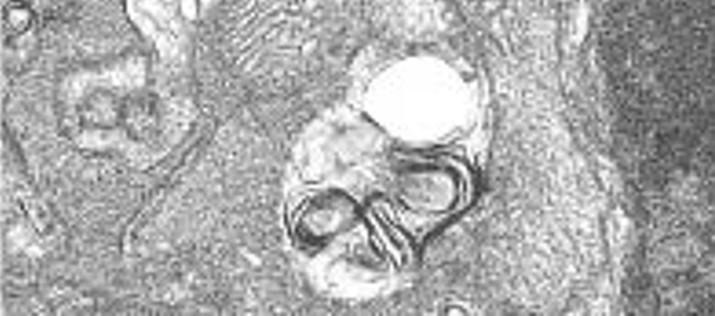

La interacción del genoma nuclear y mitocondrial determina la calidad del envejecimiento de las personas